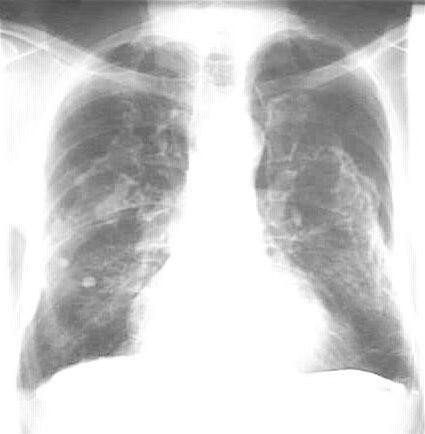

Røntgen av lungene kan vise småflekkete og stripeformede fortetninger, gjerne lokalisert til de nedre deler av lungene. Røntgenundersøkelsen fanger opp 85-90 prosent av alle med asbestose og bare 5-10 prosent får feilaktig denne diagnosen (spesifisitet 90-95 prosent). Enda sikrere diagnose stilles med høyoppløselig CT.